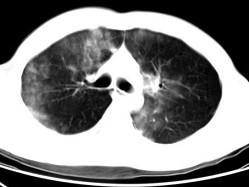

男,28岁,外伤后1小时行胸部CT如图,其最可能的诊断为 ( )A、肺癌B、双肺挫伤C、肺脓肿D、肺囊肿E、肺炎

问题 男,28岁,外伤后1小时行胸部CT如图,其最可能的诊断为 ( )

选项 A、肺癌 B、双肺挫伤 C、肺脓肿 D、肺囊肿 E、肺炎

答案 B